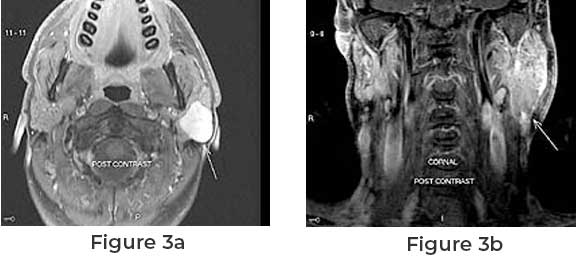

What Is Pleomorphic Adenoma Of The Parotid Gland? Expert Answers For Patients In The USA

Pleomorphic adenoma is the most common type of benign tumor found in the salivary glands, especially the parotid gland located near the jaw and in front of the ear. Although not cancerous, this condition requires medical evaluation because it can grow gradually and affect nearby structures. Many patients in the USA encounter this diagnosis duringContinue reading “What Is Pleomorphic Adenoma Of The Parotid Gland? Expert Answers For Patients In The USA”